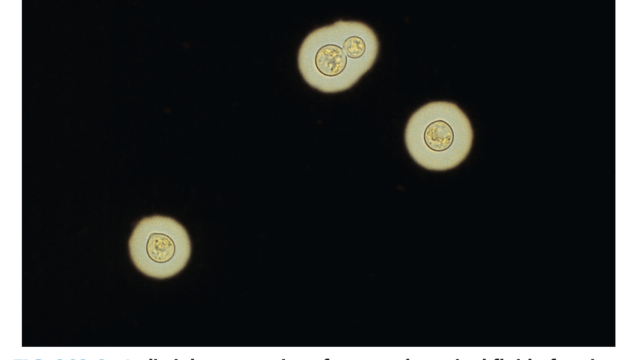

クリプトコッカス髄膜炎